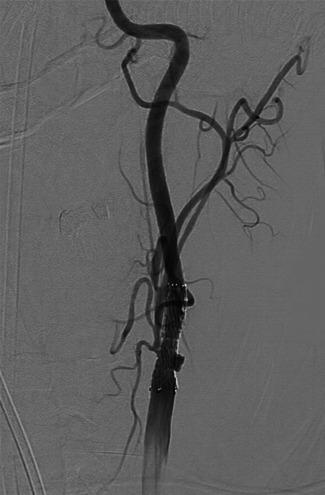

Of 5022 consecutive patients with AIS, 870 underwent EVT. Seven patients (0.8%) had EVT following cardiac surgery. Operations varied: two coronary artery bypass grafting (CABG), two transcatheter AVR, one redo surgical aortic valve replacement (AVR), one mitral valve repair and one patient with combined aortic and mitral valve replacements and CABG. Meantime postsurgery to stroke symptoms onset was 3 days (range 0-9 days). Median NIHSS was 26 (range 10-32). Five patients had middle cerebral artery occlusion and two internal carotid artery (n = 2). Median time between onset of symptoms and recanalization was 157 min (range 97-263). Two patients received Intra-arterial Thrombolysis. All patients survived and were discharged to another hospital (n = 3), home (n = 2), or rehabilitation facility (n = 2). Median 3-month mRS was 3 (range 0-6).

在 5022 例连续 AIS 患者中,870 例行 EVT。7 例(0.8%)在心脏手术后行 EVT。手术类型多样:2 例冠状动脉旁路移植术(CABG)、2 例经导管主动脉瓣置换术(AVR)、1 例再次外科主动脉瓣置换术(AVR)、1 例二尖瓣修复术和 1 例主动脉瓣和二尖瓣置换术联合 CABG。同时,术后至卒中症状发作时间为 3 天(范围 0-9 天)。NIHSS 中位数为 26(范围 10-32)。5 例患者大脑中动脉闭塞,2 例颈内动脉闭塞(n=2)。症状发作至再通的中位时间为 157 分钟(范围 97-263)。2 例患者接受了动脉内溶栓治疗。所有患者均存活并出院至另一家医院(n=3)、家中(n=2)或康复设施(n=2)。中位 3 个月 mRS 为 3(范围 0-6)。